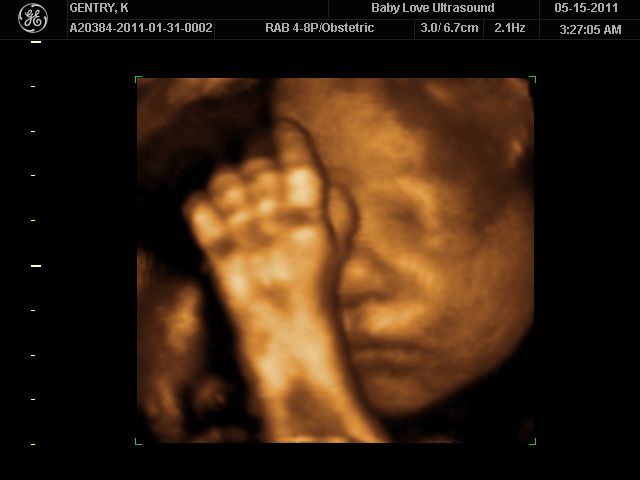

3d Ultrasound Images In San Antonio Tx